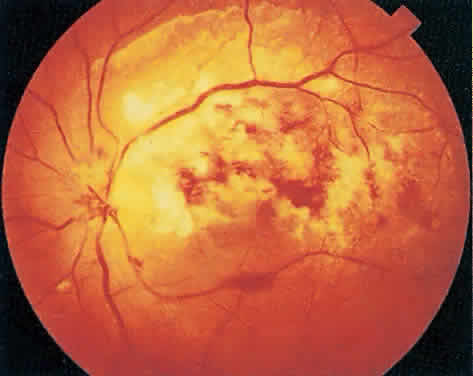

Over a course that usually spans weeks, infiltrates of CMV tend to assume two different patterns of clinical disease.11,12 The first pattern is called hemorrhagic and is characterized by broad geographic zones of retinal whitening. These large, geographic lesions are usually in close proximity to a major retinal blood vessel or the optic nerve. Satellite lesions are common. When the retinal necrosis associated with CMV retinitis becomes widespread, it is almost invariably associated with retinal hemorrhages. Although the border between necrotic and unaffected retina is sharply demarcated, the border itself appears irregular and jagged. Exudation into the retina or subretinal space may be seen, adding to the granular appearance of the retinitis. Juxtaposition of large zones of white, granular necrosis with those of red retinal hemorrhage has led this appearance of CMV retinitis to be described as either “pizza-pie” or “cheese and ketchup.” The retinal blood vessels, both arteries and veins, in the areas of necrosis commonly appear sheathed, secondary to a vasculitis. As a consequence, secondary retinal vascular occlusions, especially branch retinal vein obstructions, may occur in the course of CMV retinitis. Immune-mediated vascular damage may play a role in the vasculitis.12 Central healing of these lesions will occur as the infection progresses. Avasculitis resembling “frosted branch angiitis” hasbeen reported (Fig. 2).28 A second pattern of CMVretinitis has been labeled “granular” or “brushfireborder.” In this appearance, the focal granular infiltrates enlarge slowly across a line, leaving ever-increasing areas of destroyed retina and atrophic retinal pigment epithelium behind. Hemorrhages and vitreous cells are a less prominent feature. There appears to be direct cell-to-cell transfer of infected virions in this pattern of infection (Figs. 3 and 4). The brushfire border is commonly seen in CMV retinitis lesions anterior to the equator (Fig. 5). The significance, if any, of these two clinical patterns of CMV retinitis is not known, and, in some eyes, both patterns of disease can be seen simultaneously or in sequence. Progression of retinitis has been defined in clinical trials as movement of a lesion border at least 750 μm along a front that is 750 μm or more in length, development of a new CMV lesion in a previously involved eye or in the uninvolved fellow eye of a patient with baseline unilateral disease.29 Without treatment or improvement in the host's immune system, CMV retinitis is a relentless, slowly progressive infection resulting in blindness caused by total retinal necrosis, retinal detachment, or optic nerve involvement, in any combination.

CMV infection can affect the optic nerve either directly or by extension from adjacent retinitis (see Fig. 2).30–32 When direct involvement occurs, optic neuritis with profound, irreversible visual loss usually develops. Several cases of CMV optic neuritis associated with adjacent retinitis have been treated successfully. Exudative retinal detachment can occur during the course of CMV retinitis as well.4,12,30 The subretinal fluid is seen primarily inferiorly in the fundus and shifts with position. No retinal break will be evident; however, in areas of extremely thin, atrophic retina, it can be quite difficult to determine whether a full-thickness defect is present. Exudative retinal detachment associated with CMV is usually nonprogressive and may respond to ganciclovir therapy.